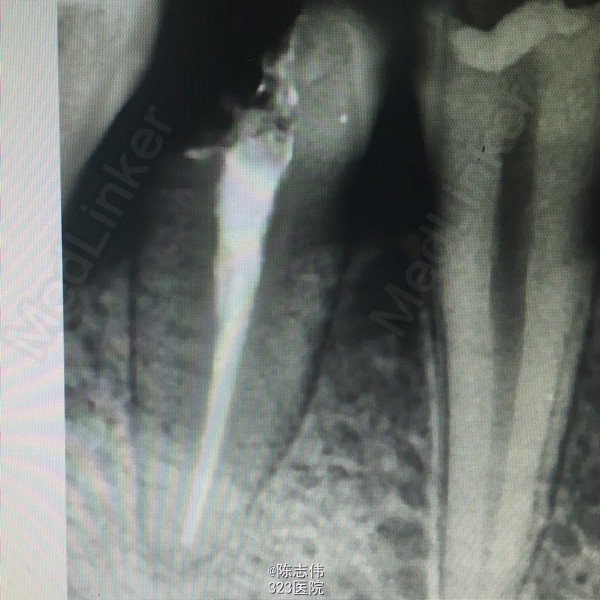

16近中颊部龋损,探深及龈下1mm,颌面白色充填物,冷(+) 松动(-) 叩(-)

x线示:16龋损近髓

印诊:16深龋

建议:16充填治疗,若露髓则行RCT

处理:局麻下16,17,45去龋,16龋净未露髓,清理干燥隔湿后垫底+3M树脂充填。17,45揭开髓室顶,丁香油棉开放,降颌